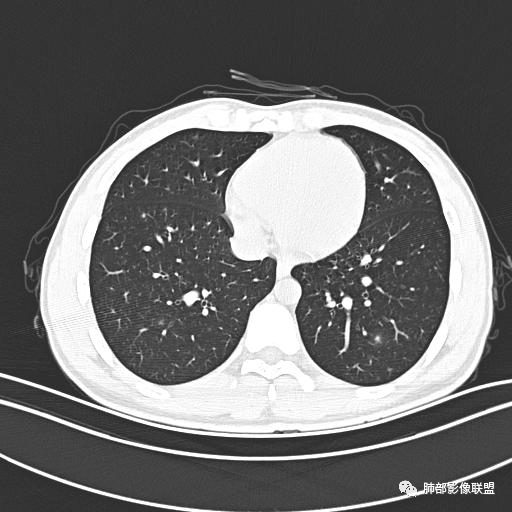

男,19岁

主  诉:发热、全身皮疹2天。

现病史:患者源于2天前受凉后出现发热,最高体温为38.5℃,且颜面部出现少量皮疹,无鼻塞、流涕、咳嗽、咳痰,未在意而未作特殊处理,次日全身皮疹逐渐增多至全身,伴轻度瘙痒,在当地卫生所给予抗病毒、抗感染治疗(具体用药不详)体温有所下降,但皮疹无明显消退,无腹痛、头痛,食欲无明显减退,为进一步诊治,遂于今日急来我院求治,患者目前精神尚可,体力正常,食欲正常,睡眠正常,体重无明显变化,大便正常,排尿正常。

小强:青年,发热,皮疹;双肺散在结节,周围磨玻璃,点晕征,疱疹病毒感染,鉴别荚膜组织胞浆菌,结核。 大雄:青年,急性起病,发热伴全身皮疹2天,抗病毒治疗体温有下降。双肺随机分布大小不等类圆结节,“点晕征”。考虑水痘-疱疹病毒(VZV)血播询问接触史,查体皮疹分布以及形态基本可诊断。 王开金江津中心医院呼吸科:青年男性,起病急,病程短,以发热,皮疹为首发症状,感染指标以单核细胞升高为主,胸部ct双肺多发结界,周围有晕,点晕表现,随机分布,同意於老师意见,水痘疱疹病毒血流感染累及肺。 王秀仙:双肺多发大小不等结节,周围有晕,边缘模糊,呈点晕征表现。青年,急性起病,发热伴全身皮疹2天,抗病毒治疗体温有下降。考虑疱疹病毒。鉴别荚膜组织胞浆菌。 傅昌瑜:19岁男性,发热、全身皮疹2天,单核细胞增高,双肺多发结节,结节边缘见边界不清磨玻璃影。点晕征+发热、全身皮疹+单核细胞增高——考虑水痘-带状疱疹病毒肺炎。 一切∮随缘:年轻男性,发热,皮疹两天,实验室,CRP,PCT增高,影像:双肺多发散在磨玻璃结节,边界欠清,大小不等,呈点晕征改变,以血管束周围分布为主,局部血管束略增粗,其它无明显改变,考虑:1:病毒性肺炎(水痘疱疹病毒?不知道皮肤有无改变)2:真菌(组织胞浆菌,血管侵袭性肺曲霉)3:GPA4:寄生虫(实验室没有看到嗜酸细胞增高) 赵山河:双肺散在结节,周围有晕,边缘模糊,呈点晕征表现。青年,急性起病,发热伴全身皮疹2天,抗病毒治疗体温有下降。考虑水痘—疱疹病毒感染。洪桥爱:青年男性,发热、皮疹2天,伴瘙痒,皮疹于面部首发,之后进展至全身,虽然没有对皮疹进行描述,但是从出疹时间及皮疹进展情况,伴瘙痒,应该就是个水痘患者;CT提示双肺随机分布结节影,部分结节伴有边界不清晕征,考虑水痘血播肺。 刘强:年轻男性,急性起病,皮疹,发热,抗感染治疗体温下降,说明有效。影像表现为散在点晕征,感染类疾病谱(疱疹病毒,真菌,结核),结合年龄,皮肤皮疹,考虑水痘-疱疹病毒性肺炎。 小兜:男性,19岁,发热皮疹两天,颜面部至全身,CRP,降钙素及单核增高。CT示双肺散在小结节,周围伴磨玻璃影,点晕征,考虑为水痘-带状疱疹病毒(varicella-zoster virus,VZV)肺炎 必有路:青年,皮疹+发热+“点晕征”→水痘-疱疹病毒(VZV) 许慧良:青年男性患者,发热、皮疹2天,体温最高38.5℃,第3天皮疹扩展至全身,伴瘙痒,胸部CT:双肺多发随机分布的小结节,结节周边见边界模糊的晕征,考虑水痘病毒感染流心明智:男,19,急性起病,发热伴全身皮疹2天。出疹顺序头→全身,抗病毒有效。胸部CT:两肺多发大小不等类圆形实性小结节影,随机分布,结节周围环绕GGO,边界模糊,呈点晕征。出疹特点是关键,未提示。考虑:血播病毒性肺炎,水痘-疱疹病毒?麻疹?鉴别荚膜组织胞浆菌、TB、血管炎、寄生虫等。 浪迹天涯:病灶多为5-10mm大小结节,结节周围可见磨玻璃样的晕环,常多发,可分布于肺内任何区域,考虑水痘—带状疱疹病肺炎如果短时间内有新的一个区域浸润,更加能说明,